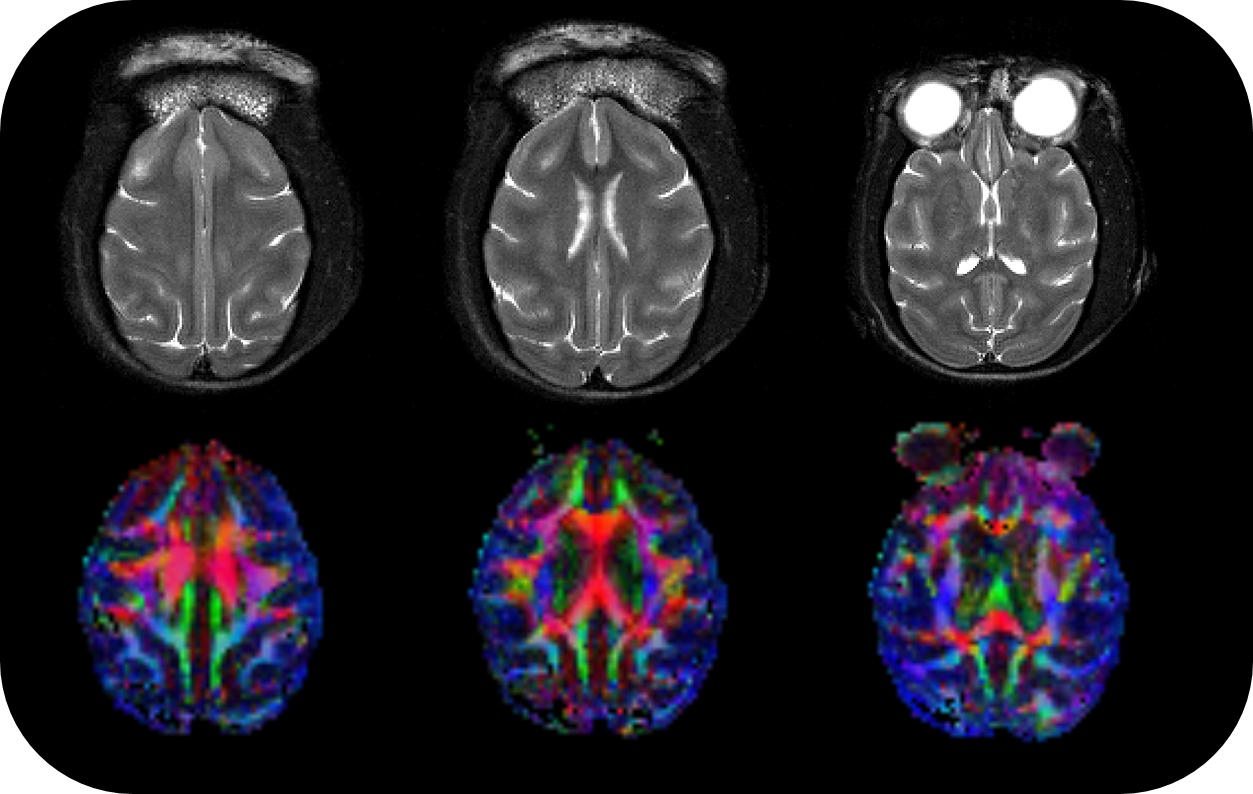

• Intuitive software package, for multi-dimensional MRI/MRS data acquisition, visualization, reconstruction, and analysis of MRI and/or PET/MR data

• MRI sequence portfolio of more than 1,000 sequence variations, including wireless cardiac imaging using navigator based IntraGate methods with cartesian or radial readout, as well as short echo time imaging, such as UTE and ZTE